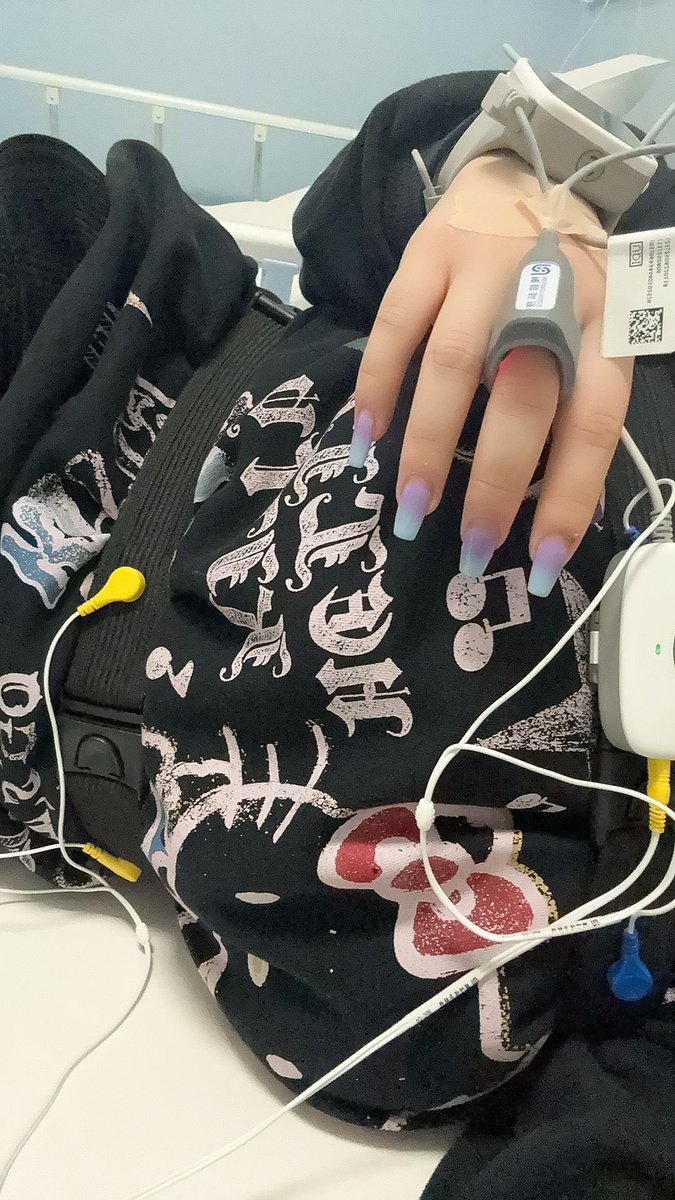

中心静脉置管留下了一片可观的淤青……而且主要分布在固定的小翅膀那里(?)

拔管的时候拆线包里的剪刀太粗了,总之一通我看不到的操作然后有一股拉扯力和剧痛和我的一声惨叫。。不知道和这有没有关系。

最后摇人拿来了手术刀片在我脖子上比划比划,然后看到拿出一根很长的管子x https://t.co/6ZTBuBOWJe

炽烈已极 @AnIncandescence消毒的时候这么痛我才看清底下那里不是胶带留的胶而是伤痕。。这里医生感觉操作好不规范啊,而且从我醒了之后就在说我左腿膝盖以下没知觉到出院也没管我没做任何检查,胸痛也没管就说痒痒,嗯没死就行是吧 https://t.co/jzkLbc6AOx